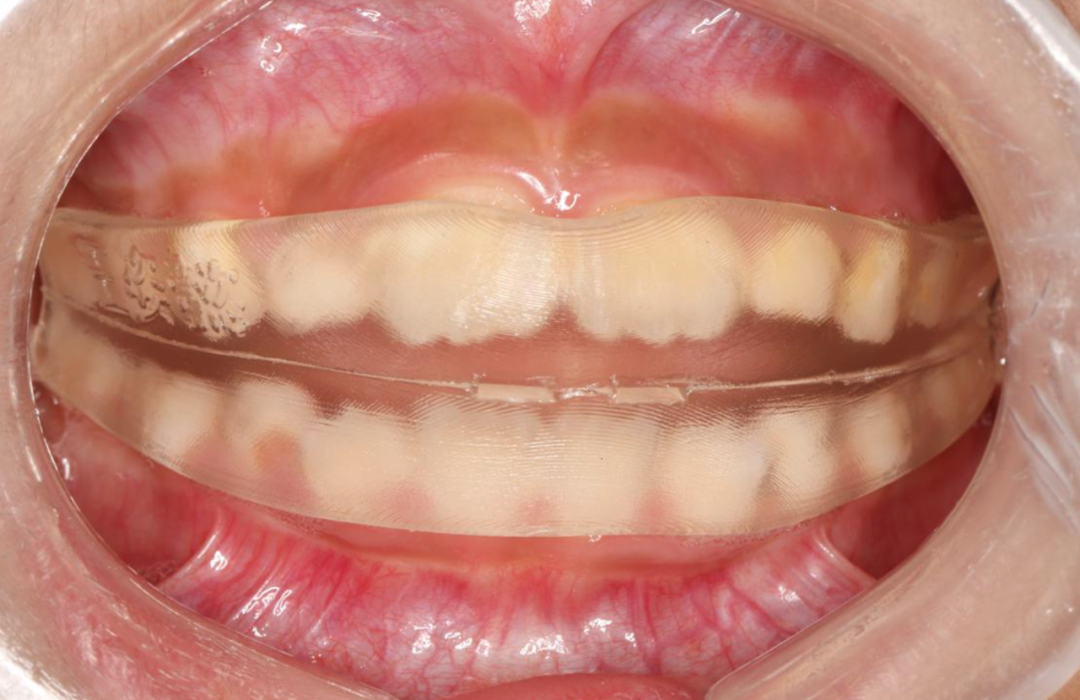

通过牙片资料检查孩子有骨性II类倾向,重度深覆合深覆盖,牙齿存在散在间隙。第一阶段佩戴隐形牙套,隐形矫正结束后,上颌内收,颏部前伸,侧貌形态改善良好,前牙达到正常覆合覆盖。

后续开展第二阶段时,将采用Grace定制化硅胶牙套,精细调整匹配上下颌弓形,整平颌平面,利用孩子生长发育潜力,继续引导下颌向前。